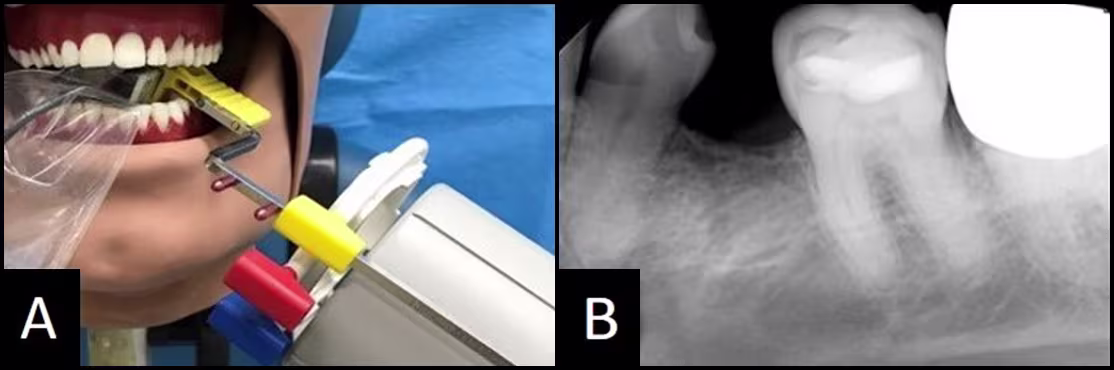

Figure 12 - Mandibular Molar Periapical: Foreshortened

(A) Sensor aiming ring, and PID are not paralleling the teeth. The vertical angulation is excessive, as evidenced by the foreshortened roots in (B)